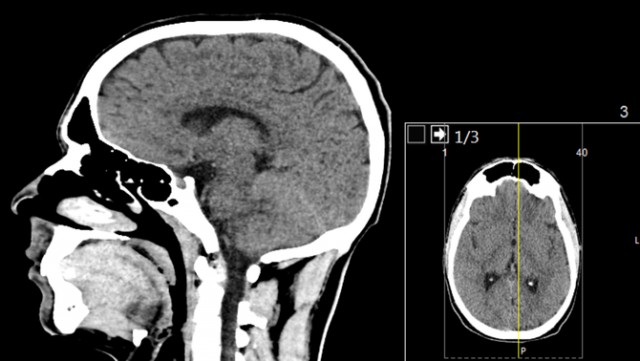

La Covid pot tenir un nou efecte secundari que fins ara era desconegut. Patir la malaltia, encara que sigui de forma lleu, pot reduir el gruix de matèria grisa del cervell, especialment en regions relacions amb la memòria i l'olfacte. A més, pot provocar una lleugera disminució de les capacitats cognitives.

Aquestes són les principals conclusions d'un estudi realitzat per investigadors d'Oxford i publicat a la revista Nature, el primer en què s'ha estudiat els canvis que provoca la infecció en el cervell. La investigació és determinant perquè l'equip del científic Gwenaëlle Douaud ha pogut examinar els escàners cerebrals de diverses persones abans i després de patir el coronavirus.

Els autors han fet la recerca amb persones registrades en el Biobank del Regne Unit, una gran base de dades biomèdiques. En aquest cas, l'estudi va incloure 785 persones de 51 a 81 anys, de les quals es tenien escàners cerebrals. D'aquests, 401 van donar positiu per Covid abans del segon escàner. La majoria dels investigats van patir la malaltia en la seva forma més lleu.

Les proves cognitives realitzades en el marc del mateix estudi constaten, però, que no hi ha afectació en la memòria després de passar la malaltia. Per altra banda, però, els investigadors d'Oxford van constatar que les persones amb Covid trigaven més temps a fer algunes tasques vinculades a l'intel·lecte.